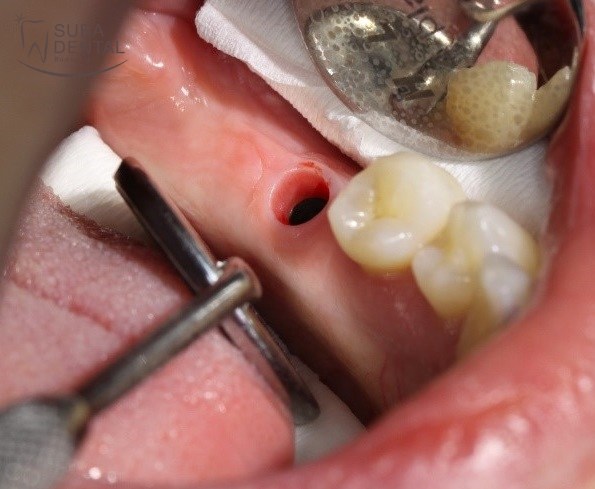

Az alsó nagyőrlő helyére beültetett DIO implantátum gyógyulási csavarral a gyógyulási idő elteltével

Az alsó nagyőrlő helyére beültetett DIO implantátum a gyógyulási csavar eltávolítása után. Jól látszik, hogy az íny nagyon szépen gyógyult a végleges felépítmény formájára